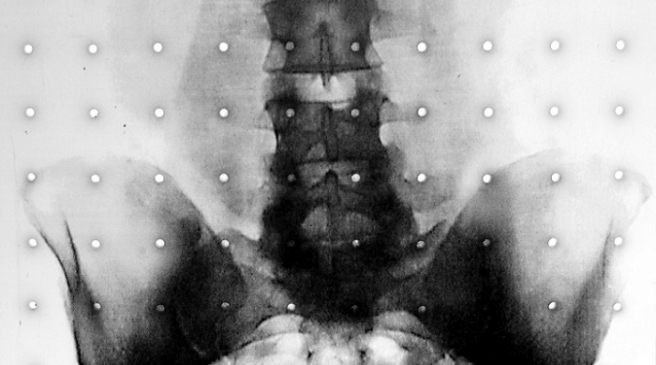

Problem sa sakroilijakalnim zglobom, SI, mjestom raskrižja u bazi kičme koji povezuje kičmeni stup s kostima zdjelice, spada u ovu drugu kategoriju uzroka križobolje, kaže dr. David Bornstein, reumatolog i profesor na sveučilištu George Washington. “Sakroilijakalni zglob je čest uzrok boli u lumbalnom dijelu leđa ali nije uvijek prepoznat i liječnici ga zamijene za druge uzroke križobolje.”

Tijelo ima dva sakroilijakalna zgloba, sa svake strane kičme. Uloga tog zgloba je da amortizira udarce i podupire težinu gornjeg dijela tijela, dok ostaje relativno stabilan. On nije kao koljeno ili lakat koji se savijaju naprijed natrag, nego je zglob koji se ne pomiče puno odnosno nije predviđeno da se pomiče.

Krut i slabo pokretan, male amplitude pokreta, predstavlja mjesto povezivanja kičmenog stupa i donje polovice tijela. Minimalna pokretljivost između kostiju koje spaja stvara velike sile opterećenja koju trpe strukture ovog zgloba. Disfunkcija ovog zgloba česti je uzrok boli u donjem dijelu leđa, stražnjici i preponama. Pacijentima je teško dulje stajati ili se penjati uz stepenice, trčati, raditi veće korake, savijati se, sjediti dulje vrijeme, skakati. Bol može obuhvatiti i noge, prepone pa i stopala.

U posljednje vrijeme bol se rješava kirurškom intervencijom koja znači ulaganje malog implantata u zglob, a to efikasno smanjuje bol i poboljšava pacijentovu pokretljivost. Novim postupkom se u zglob postavlja trokustati titanski implantat, kroz maleni rez, na taj se način zglob stabilizira i bol prestaje. piše